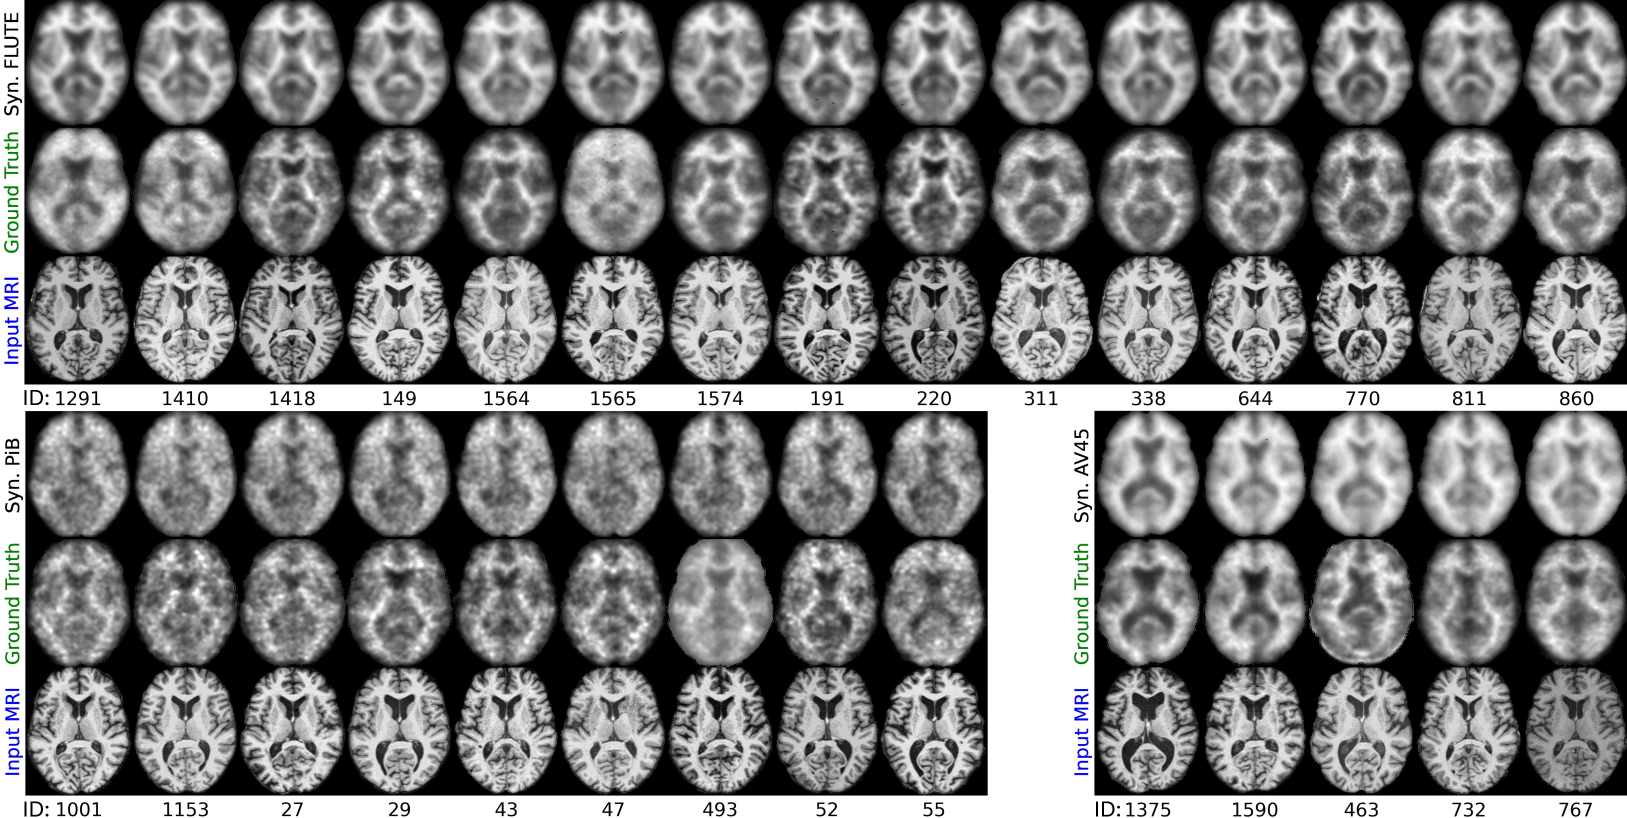

Figure 6: Visualization of synthesized PET images using the FICD for three different amyloid PET tracers: FLUTE (top), PiB (bottom left), and AV45 (bottom right), compared with the ground-truth PET images and the corresponding input MRI scans from AIBL [49].

TABLE IV: Results of fine-tuning the proposed FICD to synthesize PET images of different radiotracers from the AIBL cohort.

Radiotracer PSNR\uparrow SSIM\uparrow MAE\downarrow NMI\uparrow

AV45 22.899522.899522.899522.8995±plus-or-minus\pm±2.73522.73522.73522.7352 0.85270.85270.85270.8527±plus-or-minus\pm±0.06430.06430.06430.0643 0.03190.03190.03190.0319±plus-or-minus\pm±0.01020.01020.01020.0102 0.73350.73350.73350.7335±plus-or-minus\pm±0.08610.08610.08610.0861

PiB 21.416021.416021.416021.4160±plus-or-minus\pm±0.99530.99530.99530.9953 0.80930.80930.80930.8093±plus-or-minus\pm±0.00960.00960.00960.0096 0.03660.03660.03660.0366±plus-or-minus\pm±0.00690.00690.00690.0069 0.71740.71740.71740.7174±plus-or-minus\pm±0.01070.01070.01070.0107

FLUTE 26.972326.972326.972326.9723±plus-or-minus\pm±1.63341.63341.63341.6334 0.90890.90890.90890.9089±plus-or-minus\pm±0.01480.01480.01480.0148 0.01940.01940.01940.0194±plus-or-minus\pm±0.00400.00400.00400.0040 0.87170.87170.87170.8717±plus-or-minus\pm±0.05420.05420.05420.0542

4.7.1 Quantitative Results

Table IV presents the quantitative results of applying FICD to amyloid PET in AIBL with three radiotracers. Note that FICD is initially trained on FDG-PET images from ADNI and fine-tuned for each radiotracer. Among them, FLUTE-PET achieves impressive results, closely paralleling those obtained with FDG-PET. The outcomes for PiB-PET and AV45-PET are relatively lower, which may be attributed to less training data and inconsistencies in image quality across different subjects scanned with different radiotracers.

4.7.2 Qualitative Results

Figure 6 shows the qualitative result of PET with the three tracers. Aligning with previous quantitative results, FLUTE-PET scans are synthesized with very high fidelity. The PiB-PET scans are not as smooth as FLUTE-PET, which is caused by the radiotracer’s characteristic that 11C for PiB-PET has a short radioactive decay half-life (20 minutes) [58]. This introduces a degree of unpredictability to the images. Despite this, synthesized PiB-PET and AV45-PET scans effectively capture detailed functional information, indicating that FICD has good generalizability. To be noted, while the synthesized images consistently maintain uniform quality, there is noticeable variability in the quality of ground-truth PET from AIBL. This is because AIBL differs significantly in the types of PET tracers used (e.g., PiB, FLUTE, and AV45). These factors introduce variability in ground-truth PET images due to different tracer kinetics and baseline metabolism patterns. This variability may influence the performance of our model, particularly in how well the model trained on one dataset (e.g., ADNI) can be applied to another (e.g., AIBL). To improve the model’s generalizability across various datasets, domain adaptation techniques [59] can be used to address differences in PET image characteristics.